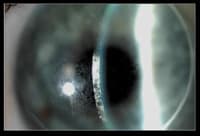

Figure 2. BH's right lens with the protein film. |

BH returned at five months complaining that the duration of his clear uncorrected vision had decreased from all waking hours to eight hours. Examination showed both lenses coated with a protein film (Figures 2 and 3).